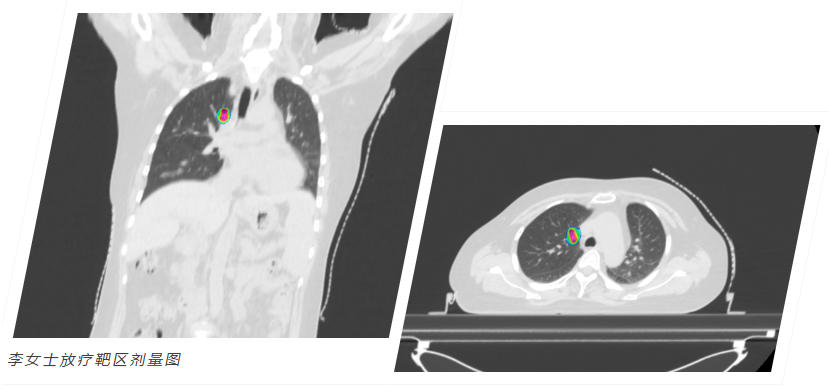

选择和祐,意味着拥抱精准与前沿。我们以多学科团队(MDT)为核心,依托全球领先的质子重离子治疗系统、超弧刀等尖端设备,结合基因检测、CAR-T等先进疗法,为患者量身定制方案。在这里,科学与关怀并重,我们全程守护,为生命希望全力以赴。